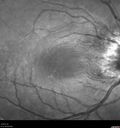

27 year old female 6 days ago she noticed she had a very bad headache and she was home trying to fix her makeup and she had the left eye closed and could not see out of the right eye. Since then she has pain behind the right eye. She has poor circulation and her hands sometimes fall asleep. In February she had a fever but did not see a doctor. (2 months ago) She had cold sweats throughout the night which lasted for just a few days. She started dating someone who has a cat for the past few months (they started seeing each other in January). She usually avoids cats because she is allergic. The cat had fleas.I have her tests which were done in the ER on two visits. Her MRI scan was negative (MS was a concern). Also, her blood work showed a slightly elevated white count with a neutropenia which was mild. The rest of her CMP and blood count was normal. Her urine catch was abnormal but had a normal culture. It had multiple epithelial cells. There were ketones and red cells in the urine. I'll have this rechecked and make sure she follows-up on the UA. VA OD: scCF 4ft PHNI NscUnable VA OS: sc20/25 NscJ1+ The right eye has disc edema and the left eye has retinitis - She was treated with Doxycycline 100 mg BID and vision returned to normal in a few months

Cat Scratch - Neuroretinitis OD AND retinitis OS - Bartonella henselae positive496 views27 year old female with exposure to cats and prior fever. Reports with recent vision loss right eye. She was treated with doxycycline and within 2 weeks the right eye looks better. Then she skipped all follow-up visits. The right eye presented 20/200 and the left 20/1600000